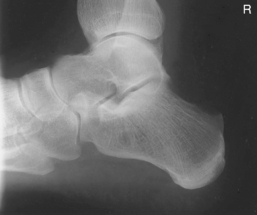

• Recumbent, turned on affected side, knee flexed with unaffected leg behind to prevent overrotation

• Place support under affected knee and leg as needed to place plantar surface of foot perpendicular to IR for a true lateral.